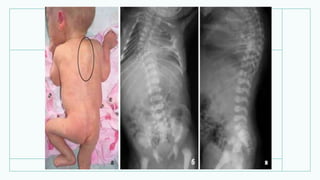

Період розпалу

• Рентгенограмма нижніх

кінцівок дитини 1 року 4

місяців: типова рахітична

деформація

великогомілкових кісток.